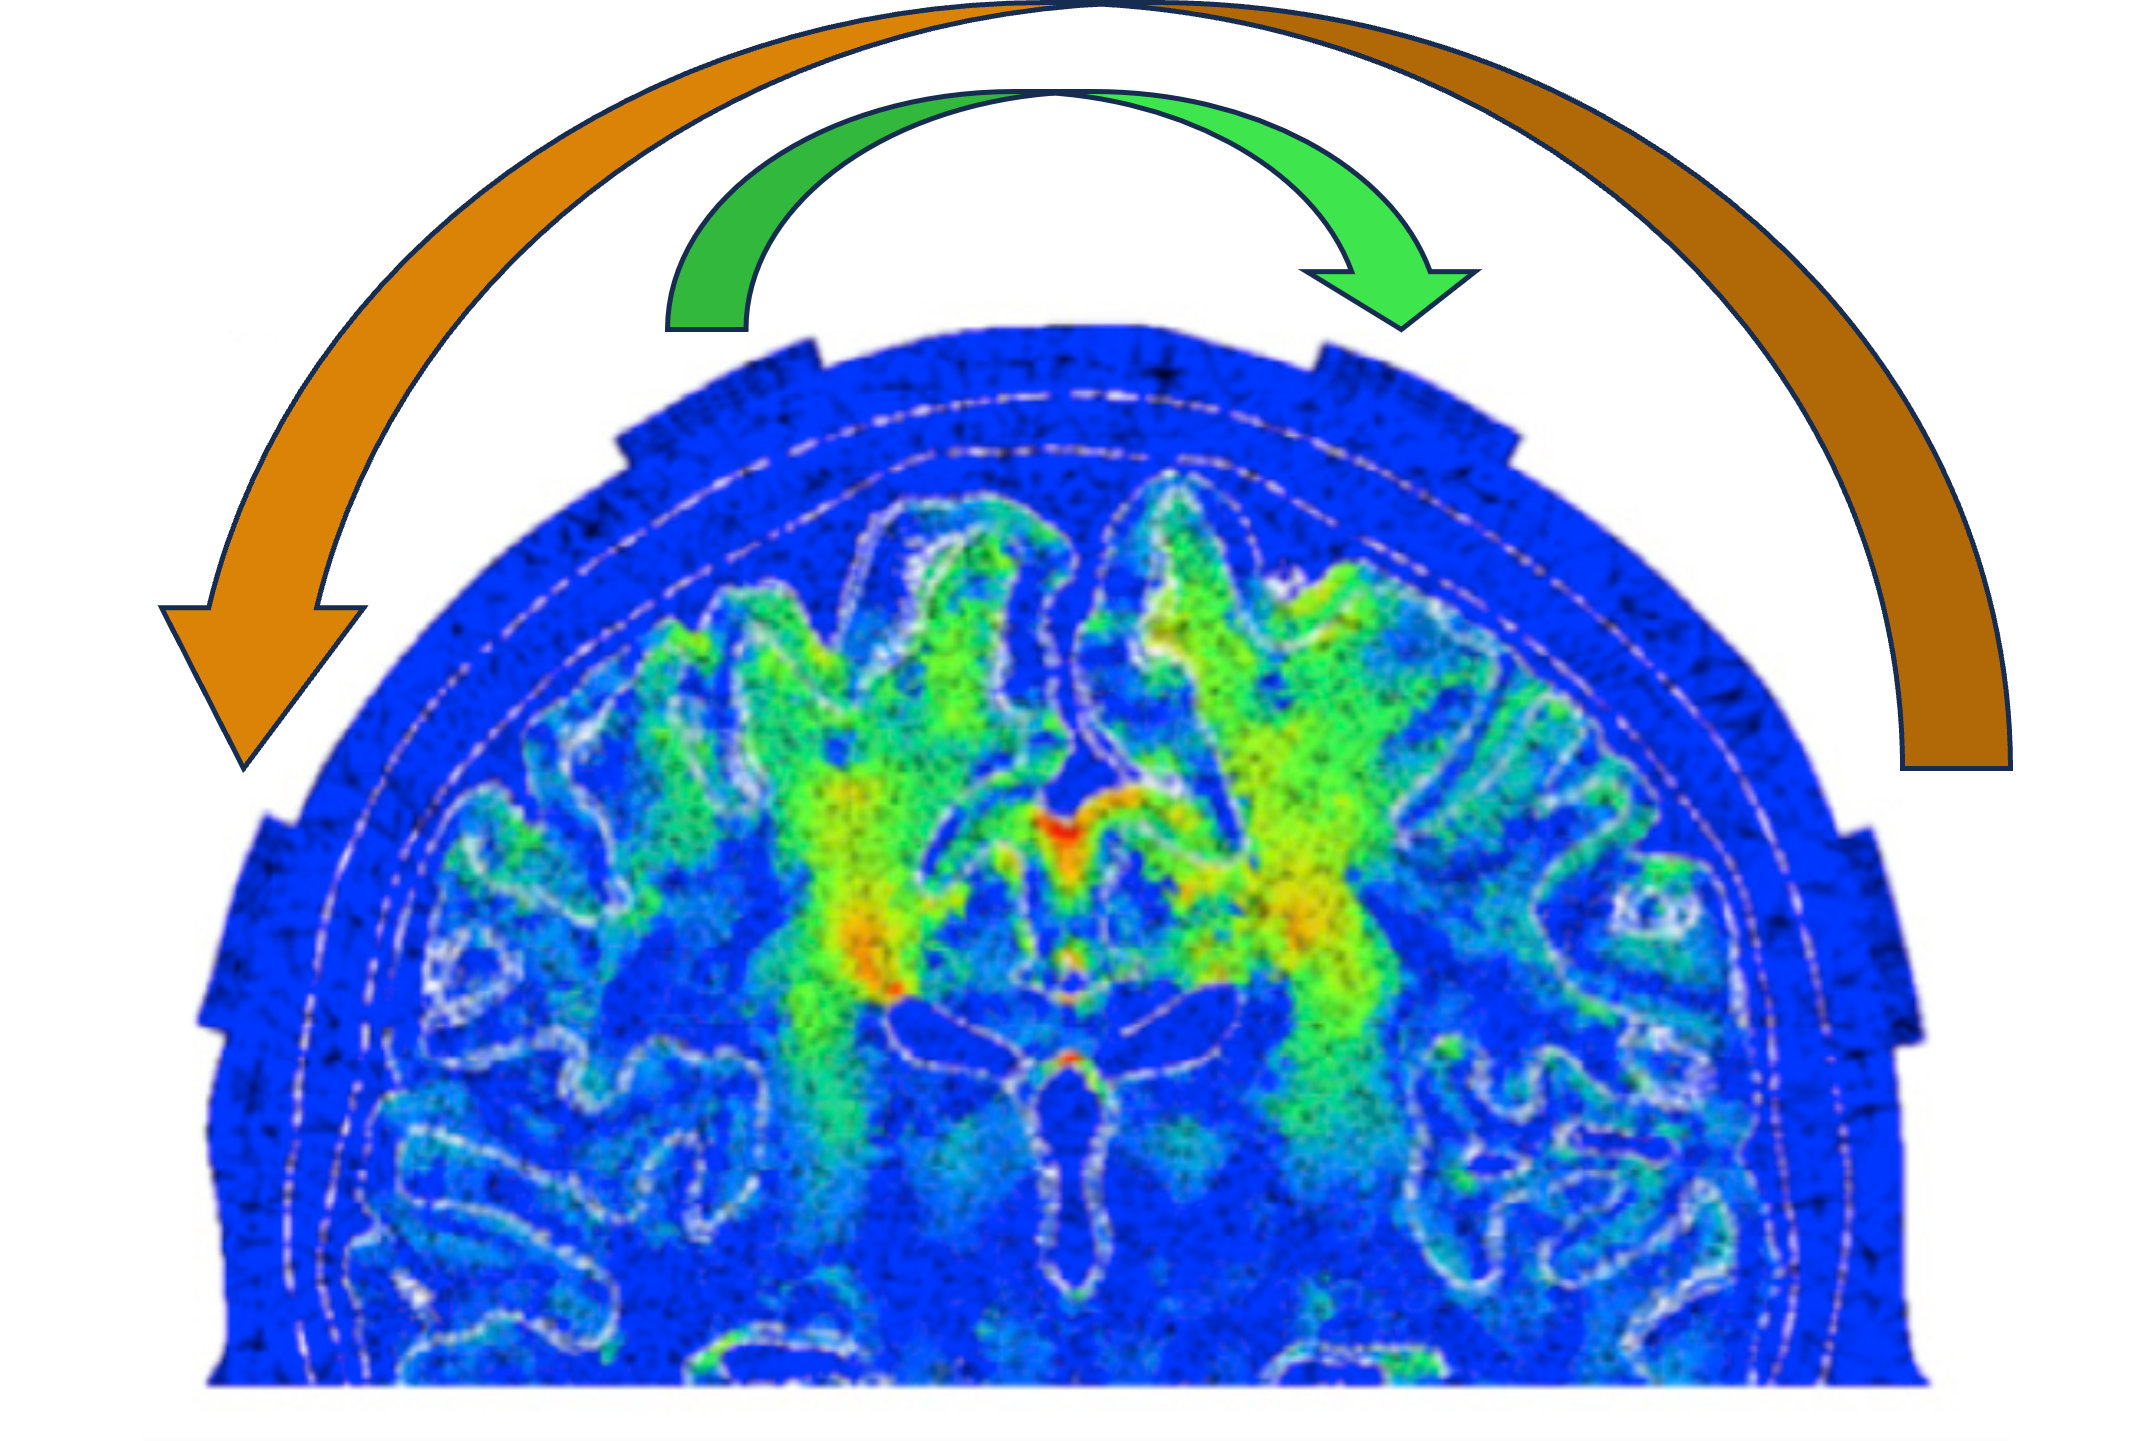

Our lab explores electrical neuromodulation: a collection of therapies in which electrical stimulation modulates neural tissue activity to alleviate neurological symptoms. While some of these therapies are performed non-invasively, others require chronic implantation of an electrical stimulator -- over a million people are living with embedded electric circuits that regularly stimulate their brain or spinal cord! Though these interventions work quite well in some patients, clinicians and scientists have a very incomplete picture of how or in whom they will alleviate symptoms. We aim to improve and expand these therapies by identifying optimal anatomical targets, understanding their behavioral and physiological responses, leveraging neural feedback to assess their efficacy, and building devices to make neuromodulation less invasive and more therapeutic for a wider range of neurological conditions.

Existing FDA-approved neuromodulatory interventions use electrical brain implants that modulate neural activity to alleviate symptoms. We work to understand and improve these therapies for and in human patients, with experimental efforts in living and computational model systems.